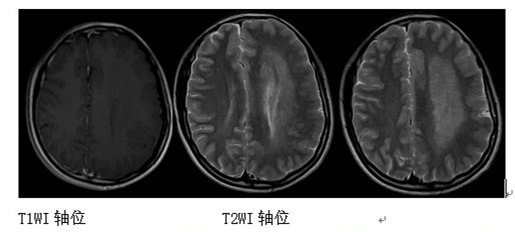

MR表现为受累侧大脑半球中到重度增大;皮质发育不良,脑回宽,脑沟浅,皮层增厚;白质信号不均匀,提示灰质异位和发育不良的神经元和胶质。

典型患者的侧脑室形状颇具特点:它按患侧半球增大的比例增大,额角伸直,指向前上方。患侧半球大多功能缺失,且可成为癫痫病因。